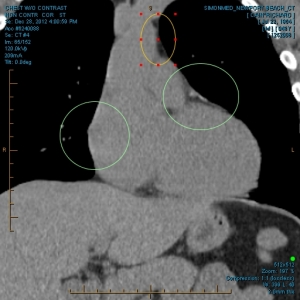

“My family and I have been the subjects of Government funded human research and/or hate crimes. These crimes are being covered-up by using the words National Security. The fact that my two minor children have the same and/or similar devices in their little bodies speaks for themselves. My sons were ages 3 and 4 when the discoveries took place. Their x-rays, blood & urine analysis present the true facts. The devices can only be introduced into the body, while being in a medical facility. All three of us were patient of the same defendant hospital.

“The CD-ROM from CCAI depicts the same images that are attached. I will bring the 01/03/2012 Simonmed Imaging CT scan which also depict foreign objets in the heart and chest.”

“Please take a look at both X-rays. Superimpose the foreign objects AKA EKG clamps and you will find that they are the same devices. when have you ever seen an EKG clamp place sideways in the abdomen? Both x-rays have been confirmed by Radiologist Louis Teresi as having foreign body reactions in the abdomen, right and left flanks.

“The obvious implant in the 2012 x-ray stands out from the others, because it at the time had not embedded into my flesh (heart).”